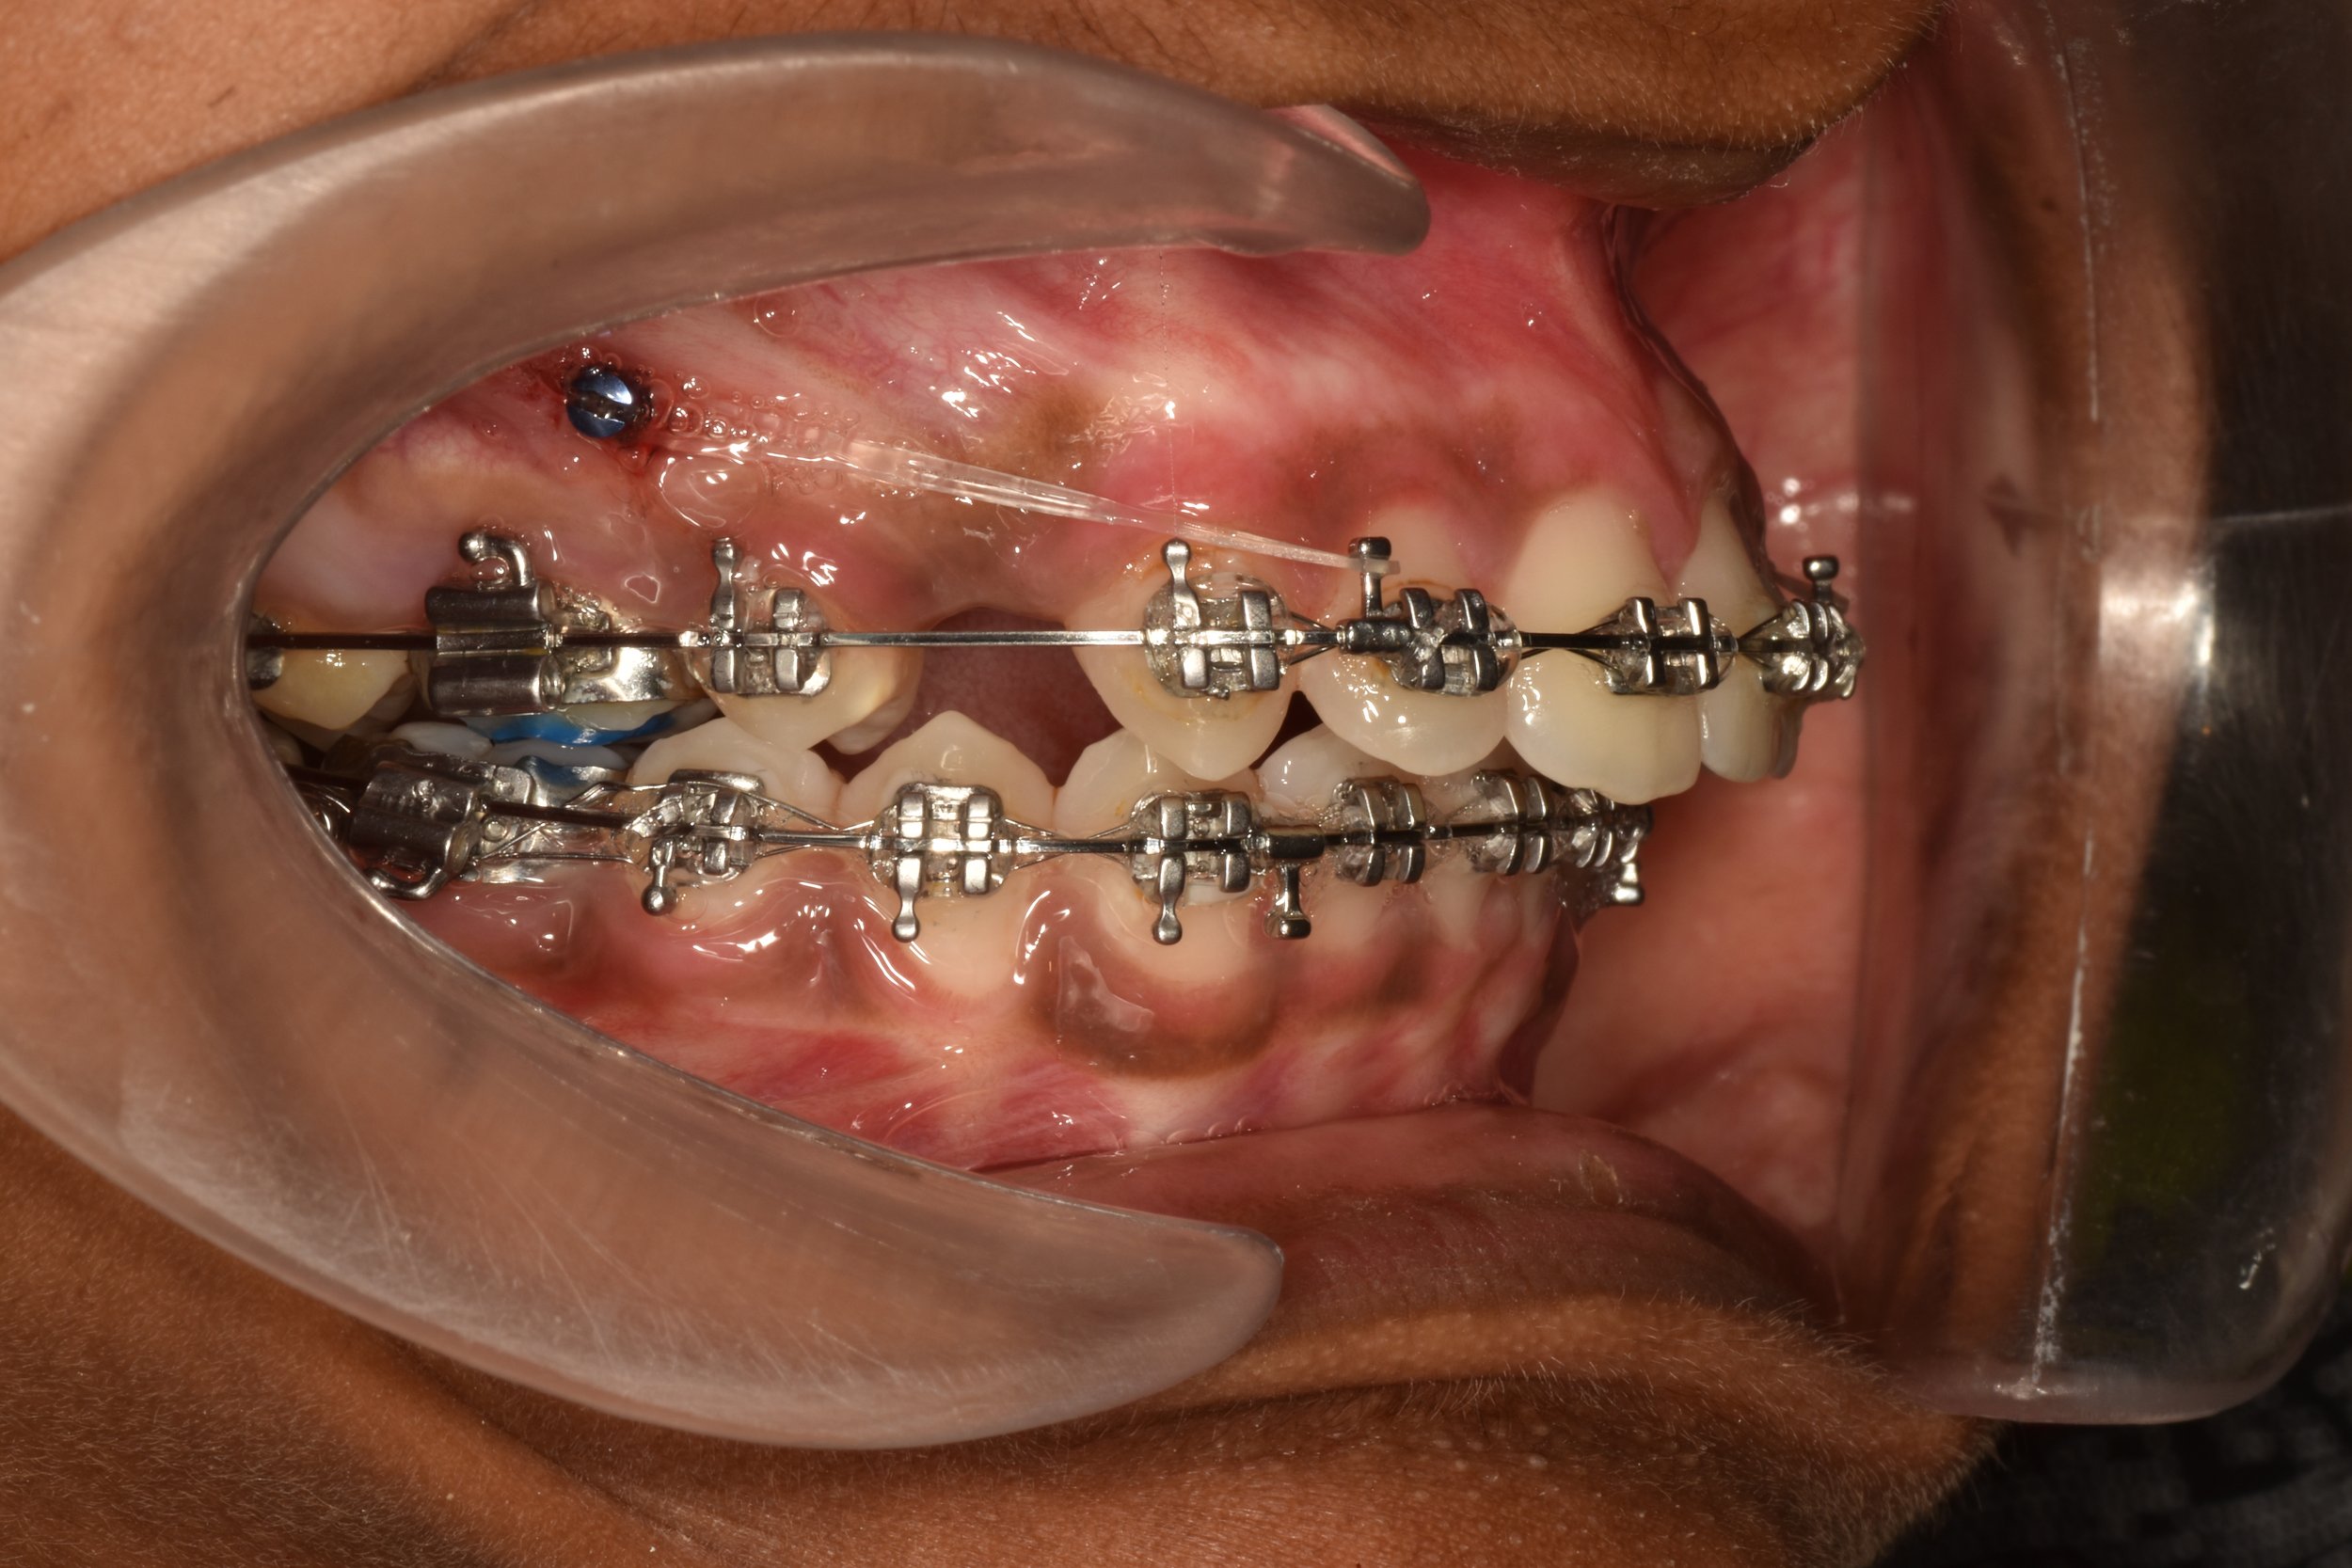

Extra-radicular implants